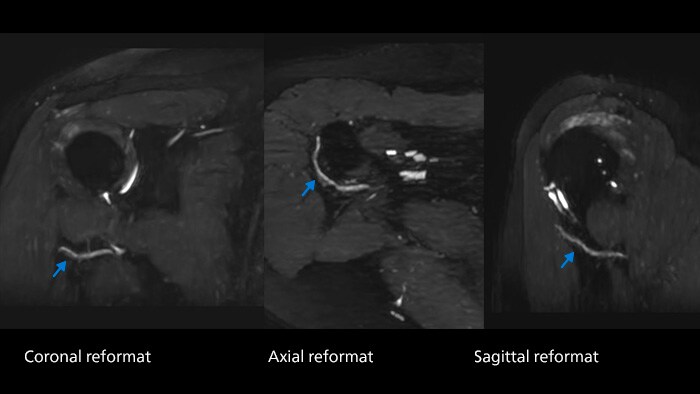

“With SmartSpeed, we’ve been able to use some extended applications more routinely. A good example is Philips 3D NerveVIEW. Being able to bring its scan time down to 3 or 4 minutes rather than 6 or 7, has allowed us to use it routinely and find answers that we haven’t achieved before. We’ve introduced it in many peripheral MSK and extracranial neural applications. Now we are seeing diagnoses of neuritis in regions that we’ve never seen previously. It’s a whole new way of looking at peripheral neurography.” As a result, Mermaid Beach receives great feedback from their referring hospitals.